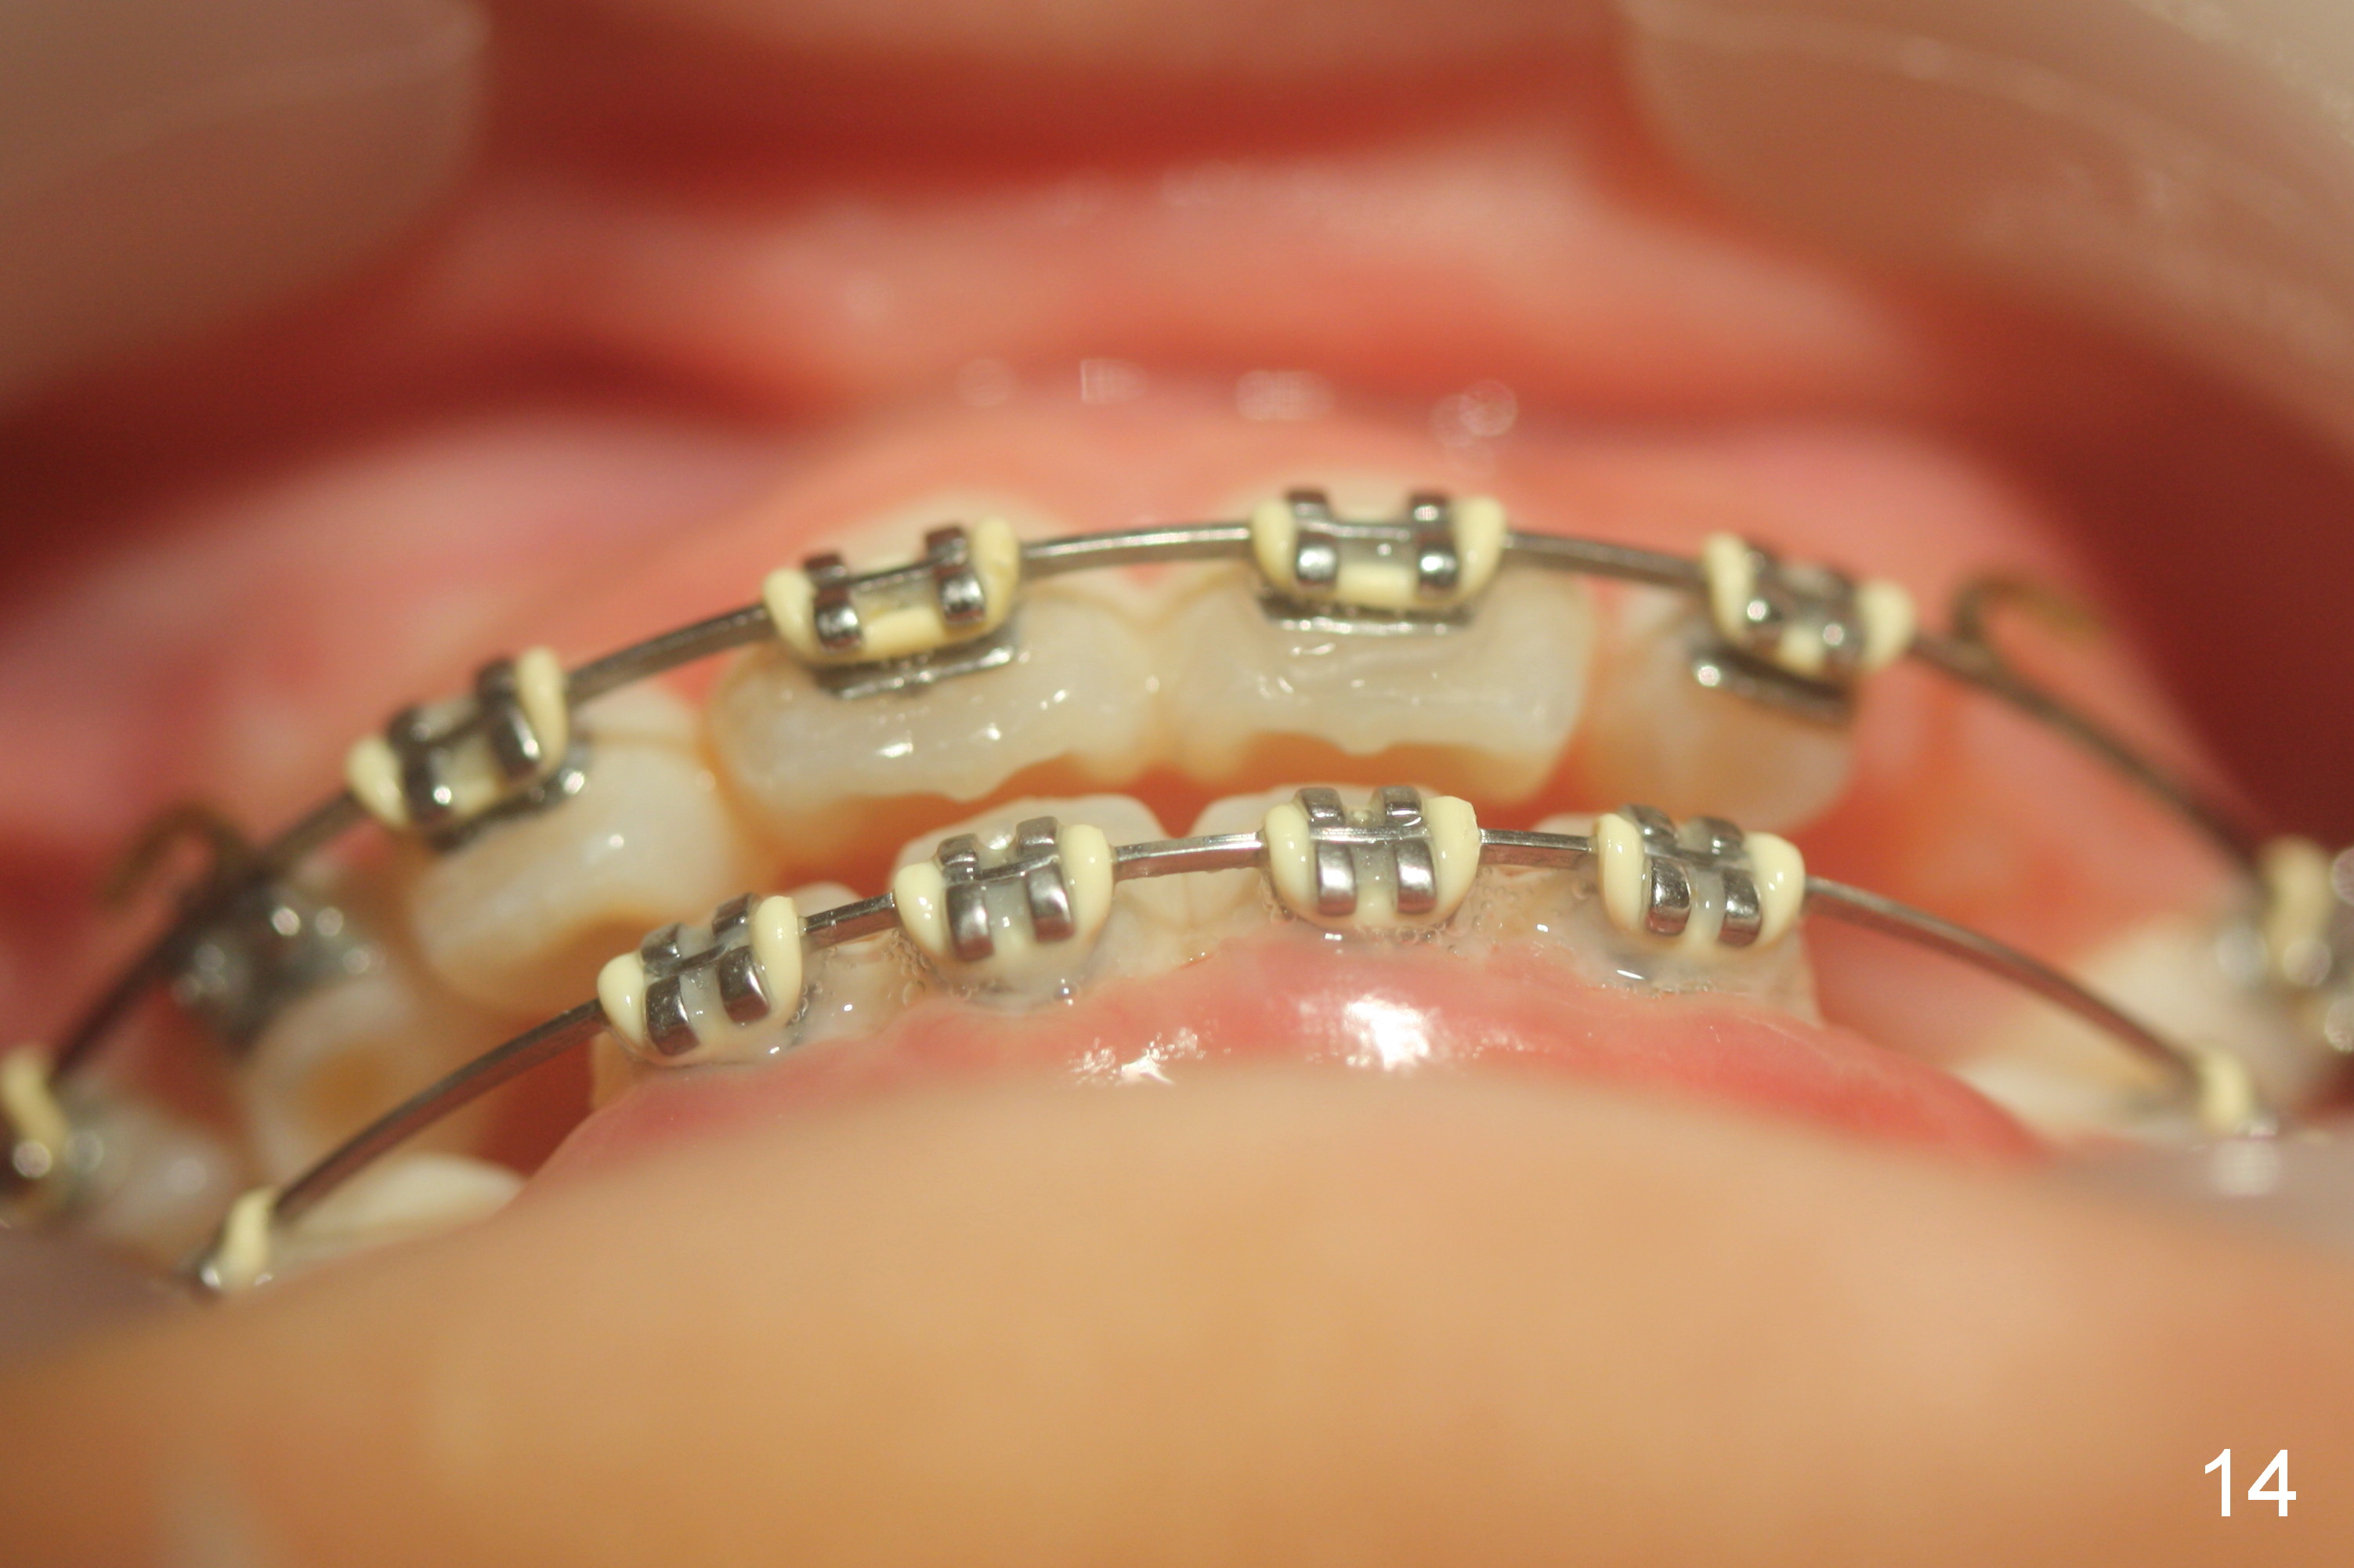

Between the 2nd and 3rd months, the patient is instructed to wear face bow after school. Overjet is WNL. Then the kit wears face bow before sleep. Fig.12-15 are taken 4 months of face bow. Can we ask the girl to wear it every night for 2 weeks and then every other night for another 2 weeks before removing brackets?

OK Xin, just evaluated the case. If she started with the anterior dental crossbite and you are barely over-corrected right now, I would be very comfortable discontinuing treatment. At her age, there is nothing that can no longer be dealt with beautifully when it is more age appropriate.When anterior cross bite is corrected 19 months post banding, the tooth #10 (microdontia) has tendency of edge-to-edge (Fig.16,17). Power chains are used to create space for #11 to erupt fully before bracketing. In spite of the effort, the peg lateral remains edge-to-edge 23 months post banding (Fig.18,19). The segmental 19x26 braided wire retains as a retainer to prevent #10 from cross bite. The facial profile is more or less normal immediately post debracketing (Fig.20). The anterior occlusion appears to remain basically the same 7 months post debracketing (Fig.21,22). UR3 erupts, while the diastema mesial to UL2 enlarges so that the arch wire appears shorter. UL2,3 appear to be in cross bite 14 months post debracketing, while Es retain at the age of 13 (delayed development, Fig.23).